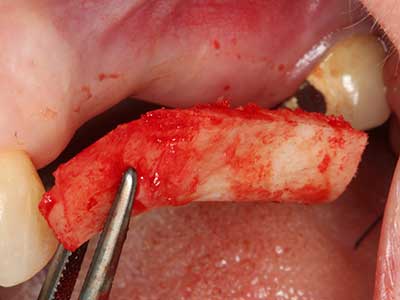

Пиезохирургията има допълнителни предимства при събиране на костни блокове. В допълнение към високата прецизност при остеотомията, описана по-горе, употребата на фините режещи накрайници значително намаляват загубата на материал. Голяма загуба на материал по време на събиране може да се очаква с дебелите накрайници, особено при употреба на борери Линдеман (Lakshmiganthan, Gokulanathan et al. 2012). Базалното разделяне, което е необходимо, особено за присадка на блок при ретромолар, е улеснено от специално създадени правоъгълни триони. В резултат на това, пиезохирургията е разглеждана като прецизна, улеснена и безопасна процедура за събиране на костни блокове в ретромоларното пространство (Happe 2007) (Фиг. 1-12).

Фиг. 3: Базалното разделяне на блока е по-лесно със специалните извити накрайници.